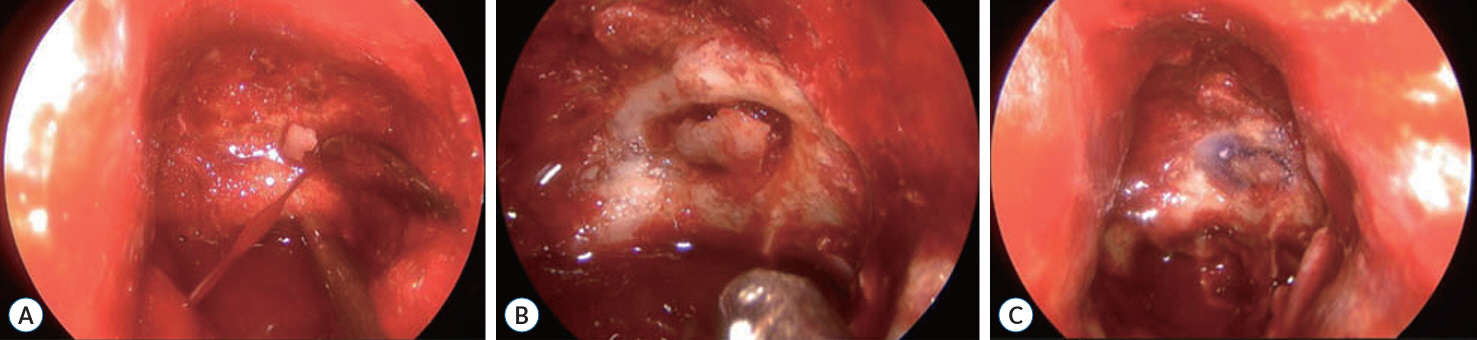

A Successful Control of the Intraoperative Bleeding from McConnell’s Artery during Fully Endoscopic Resection of Planum Sphenoidale Meningioma Using Bone Chip and Bioglue : A Case Report

- The endoscopic transsphenoidal approach is a common approach used in skull base neurosurgery to reach the sellar region. One of the intraoperative risks of this approach is intraoperative bleeding out of the carotid artery. Gentle drilling can prevent carotid artery injury. However, injury to smaller branches, such as the McConnell’s capsular artery, which is located within the surgical corridor, is more difficult to prevent. If such an injury is within the junction to the main trunk of the carotid artery, there will be a small circular defect in this area. This can result in massive blood loss and should be closed surgically immediately. We describe a clinical case of intraoperative bleeding from the McConnell’s artery originating from the carotid arterial segment (C4) in a 78-year-old female patient operated on for planum sphenoidale meningioma via endoscopic transsphenoidal approach, as well as provide a technical note on a possible technique for bleeding control in such cases. Pinpoint carotid bleeding as a result of intraoperative injury can be stopped by wedging a bone fragment in the carotid canal and fixing it in that position with histoacryl glue at the defect site.